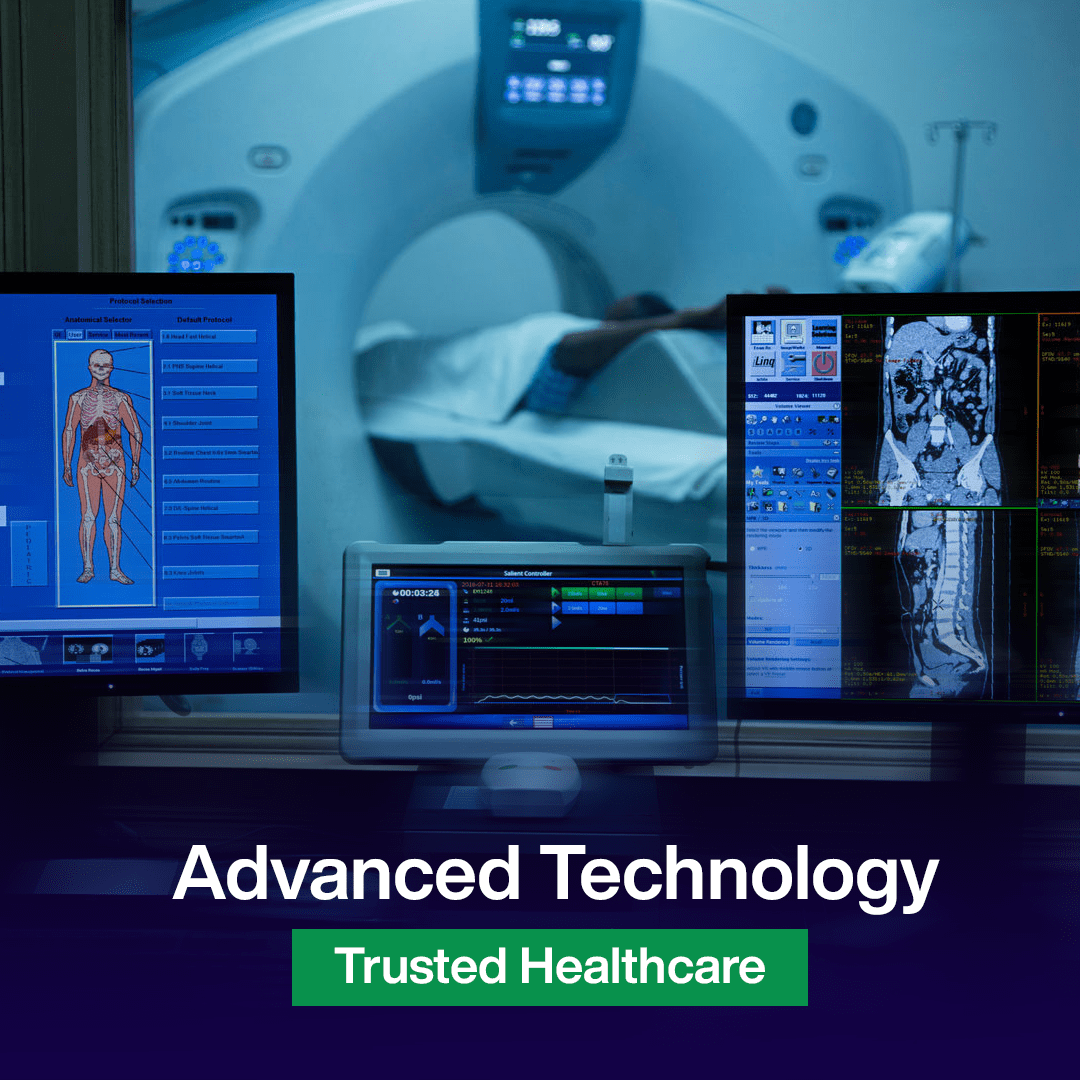

Empowering lives with advanced healthcare solutions. From diagnostics to recovery, we bring innovation and expertise together for better outcomes

JS Multispeciality Hospital brings together experienced doctors, advanced medical technology, and patient-focused care under one roof. From diagnosis to treatment, every department is designed to deliver accurate, timely, and reliable healthcare for you and your family.

Advanced imaging services supporting accurate diagnosis and timely treatment decisions across all departments. Services include: X-ray, USG, imaging consultation, diagnostic...